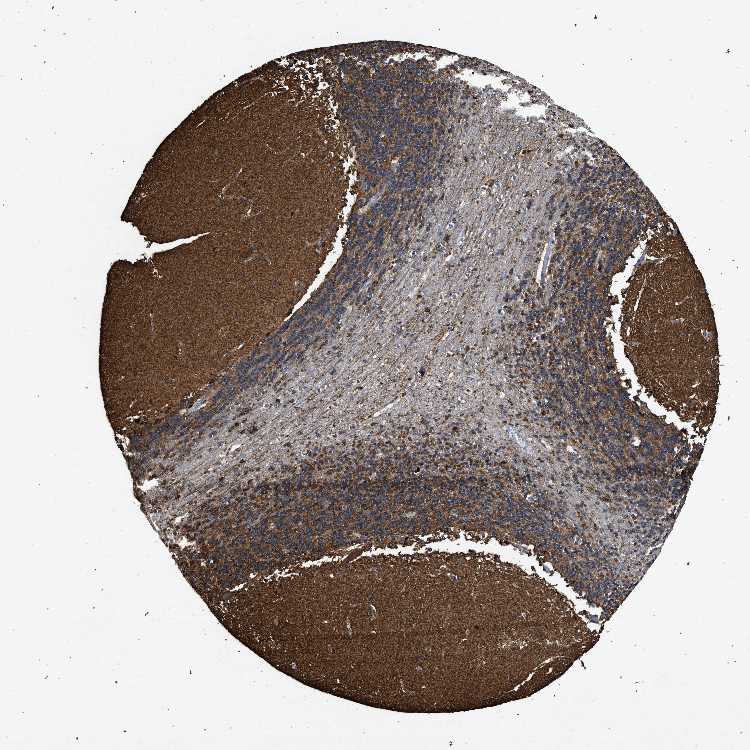

BRAIN CEREBELLUM Show tissue menu

CEREBELLUM - Expression summary

CEREBELLUM - Antibody stainingi

Antibody staining in the annotated cell types in the current human tissue is reported as not detected, low, medium, or high, based on conventional immunohistochemistry profiling in selected tissues. This score is based on the combination of the staining intensity and fraction of stained cells.

Each image is clickable and will lead to virtual microscopy that enables deeper exploration of all samples and also displays staining intensity scores, fraction scores and subcellular localization as well as patient and tissue information for each sample.

Antibody HPA067595Antibody HPA069443Antibody CAB022062

Molecular layer - neuropil -High-

Molecular layer cells - nucleus -High-

Synaptic glomeruli - core -High-